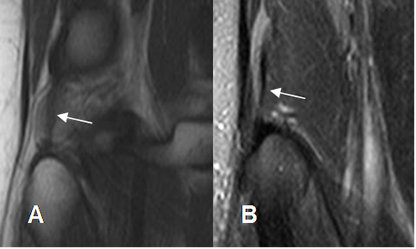

Fig 10. Tendones normales de la pata de ganso.

A: RM sagital en T1 y B: RM axial en T2. Tendón del semitendinoso (Flecha delgada), sartorio (Flecha gruesa) y recto interno (Punta de flecha).

Fig 11. Mecanismo extensor normal.

A: RM sagital en T1 y B: RM sagital en T2. Tendón del cuadriceps (Flechas gruesas) y patelar (Flechas delgadas) de aspecto normal, hipointensos en ambas secuencias.

Fig 12. Mecanismo extensor normal.

RM sagital en T1. Zonas hipointensas en el tercio proximal del tercio proximal y distal del tendón patelar, por variante normal.